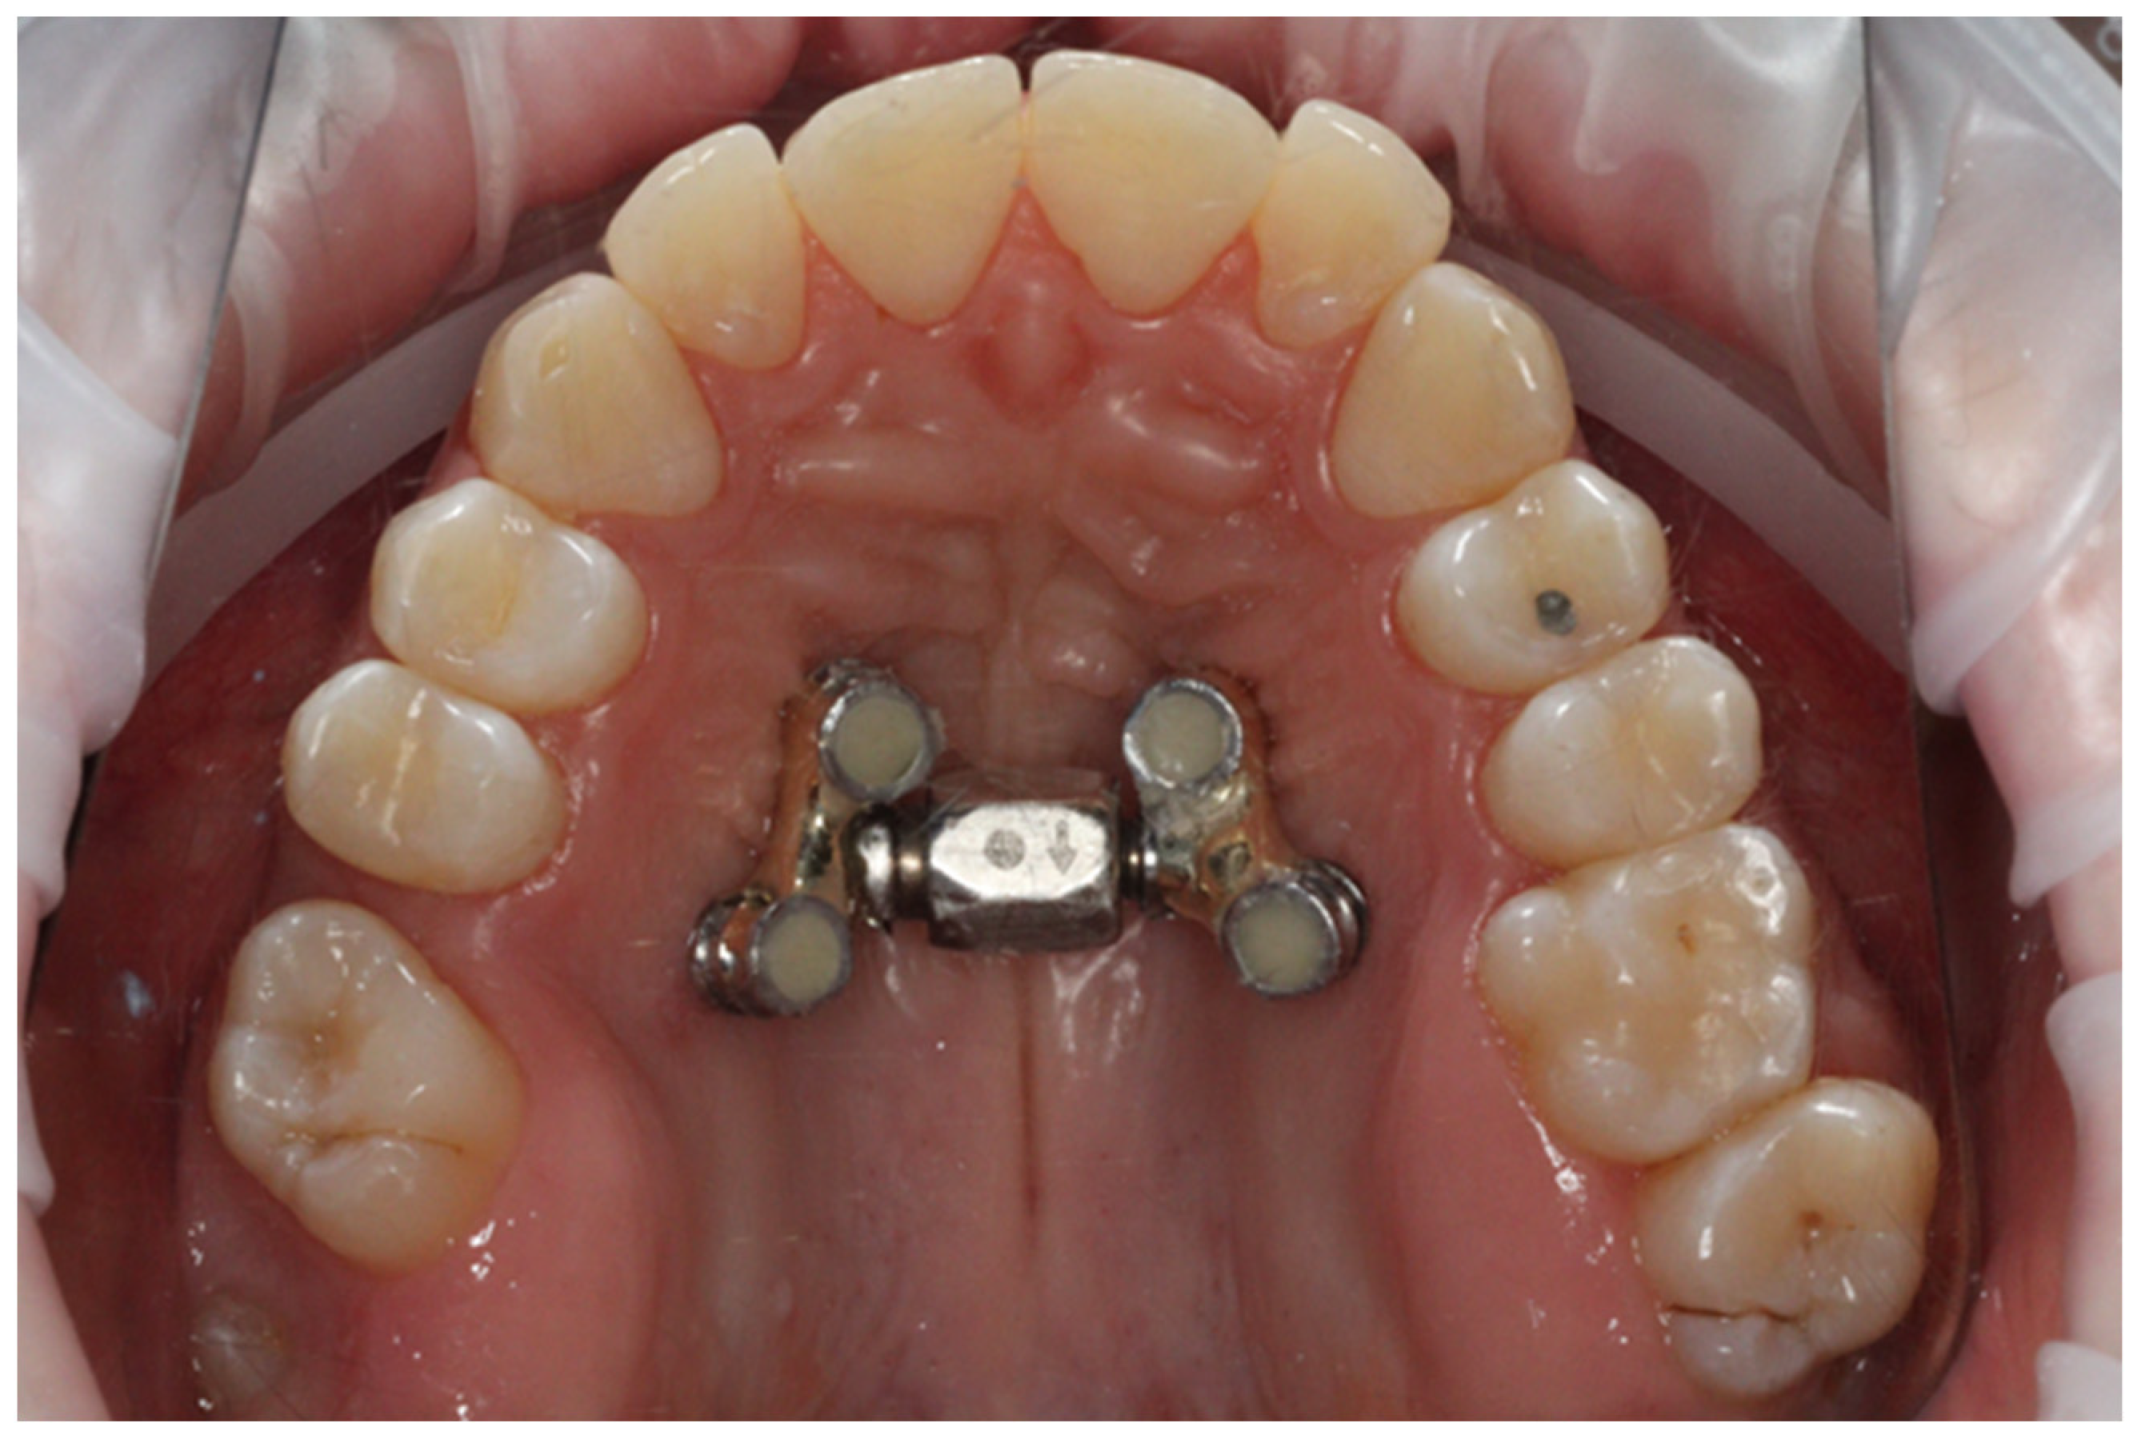

- Following cone beam computed tomography (CBCT) examination and analysis of the intended location of the mini-implant, the temporary orthodontic implant screws were inserted under local anesthesia. Dual-Top JS jet screw implants (Tiger Dental, Bregenz, Austria) with a diameter of 2.5 mm were used. Four implants were inserted in each patient: two mesially and two distally. Depending on the amount of bone available, implants of 12, 14, or 16 mm in length were inserted by the same operator (BWL).

- After two weeks of the healing, an alginate impression with transfers caps was taken. A master cast was produced in the in-house laboratory from Class IV plaster with four laboratory analogues. The distractor size was chosen based on the clinical situation (the available screw body sizes were 8 mm, 10 mm, 12 mm, 14 mm, and 16 mm). We refer to the appliance as the PS4 Distractor, after the Power Screw (PS) and the number of implants on which it was placed. The master cast with the selected screw and four collars for adhesive bonding was sent to the laboratory. All distractors were made in the same laboratory (Ortolab, Częstochowa, Poland).

- After a further three weeks, the distractor was cemented onto the implants using SDI Riva Self Cure HV Glass Ionomer (Melbourne, Australia) cement by the same operator (BWL). An example is presented in Figure 1.